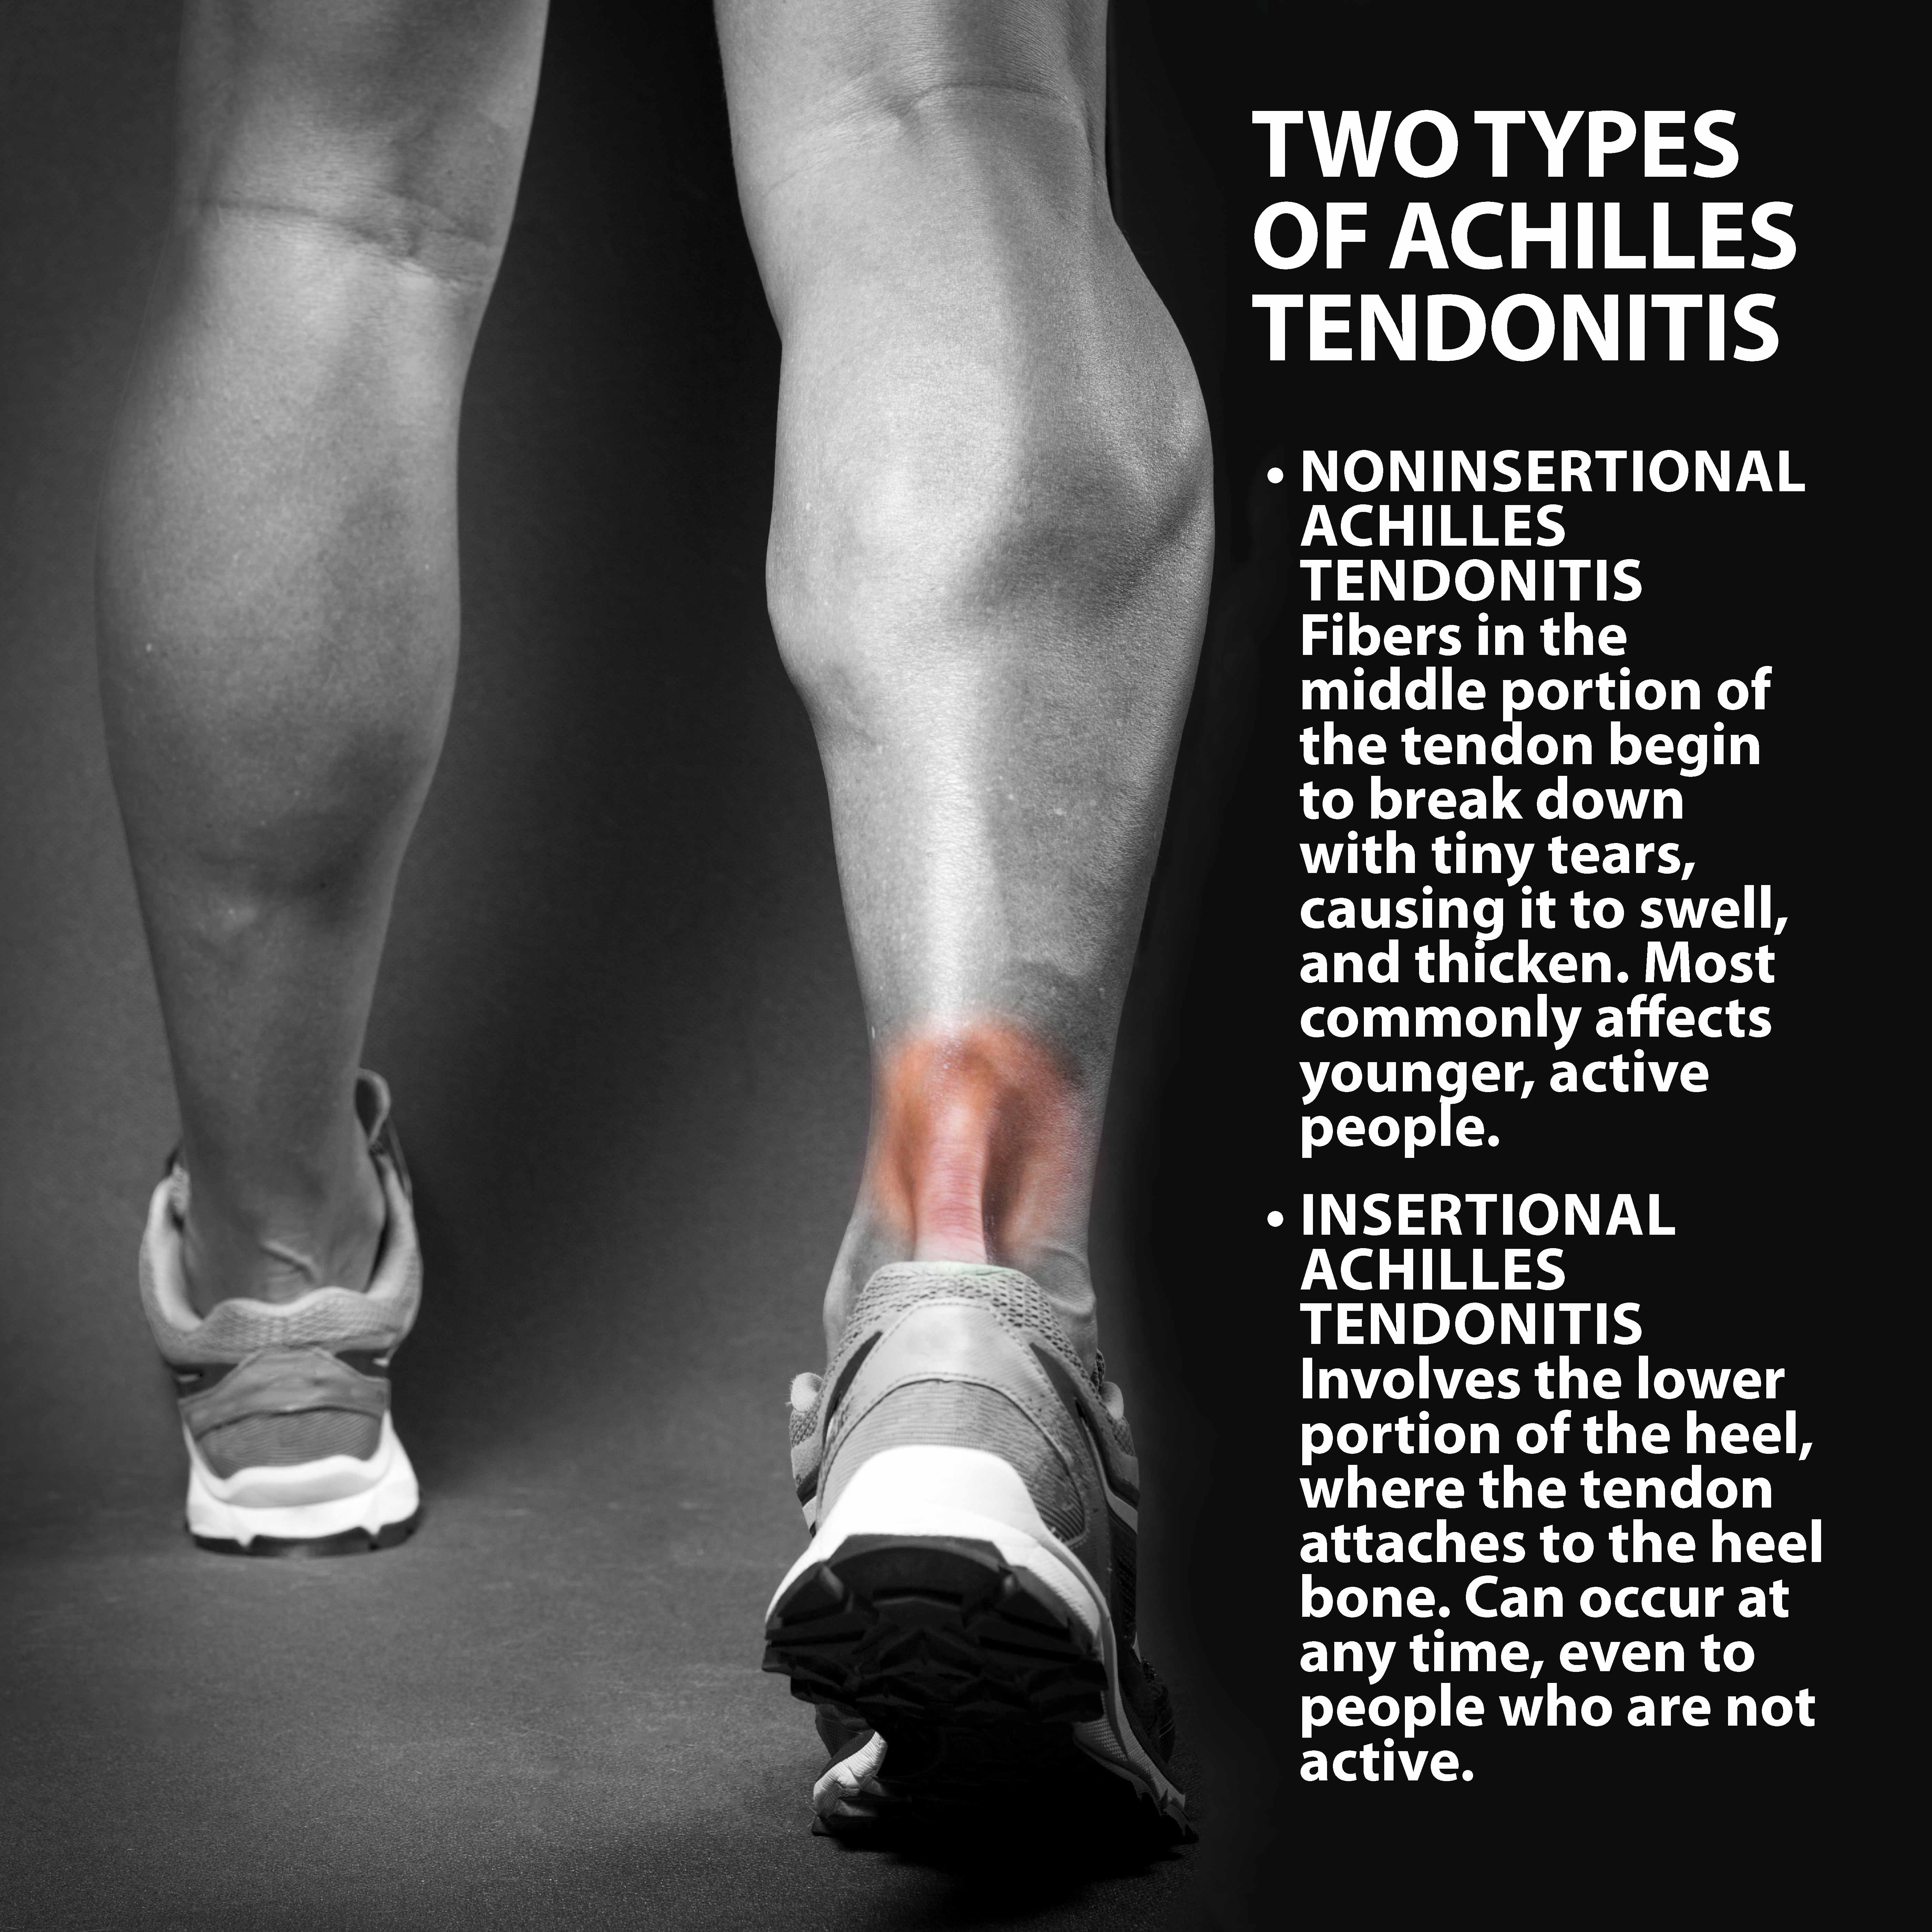

Achilles Tendinitis Info | Florida Orthopaedic Institute

Achilles Tendonitis Basics | Florida Orthopaedic Institute

Achilles Tendinitis Info | Florida Orthopaedic Institute

Achilles Tendinitis – OrthoInfo – AAOS